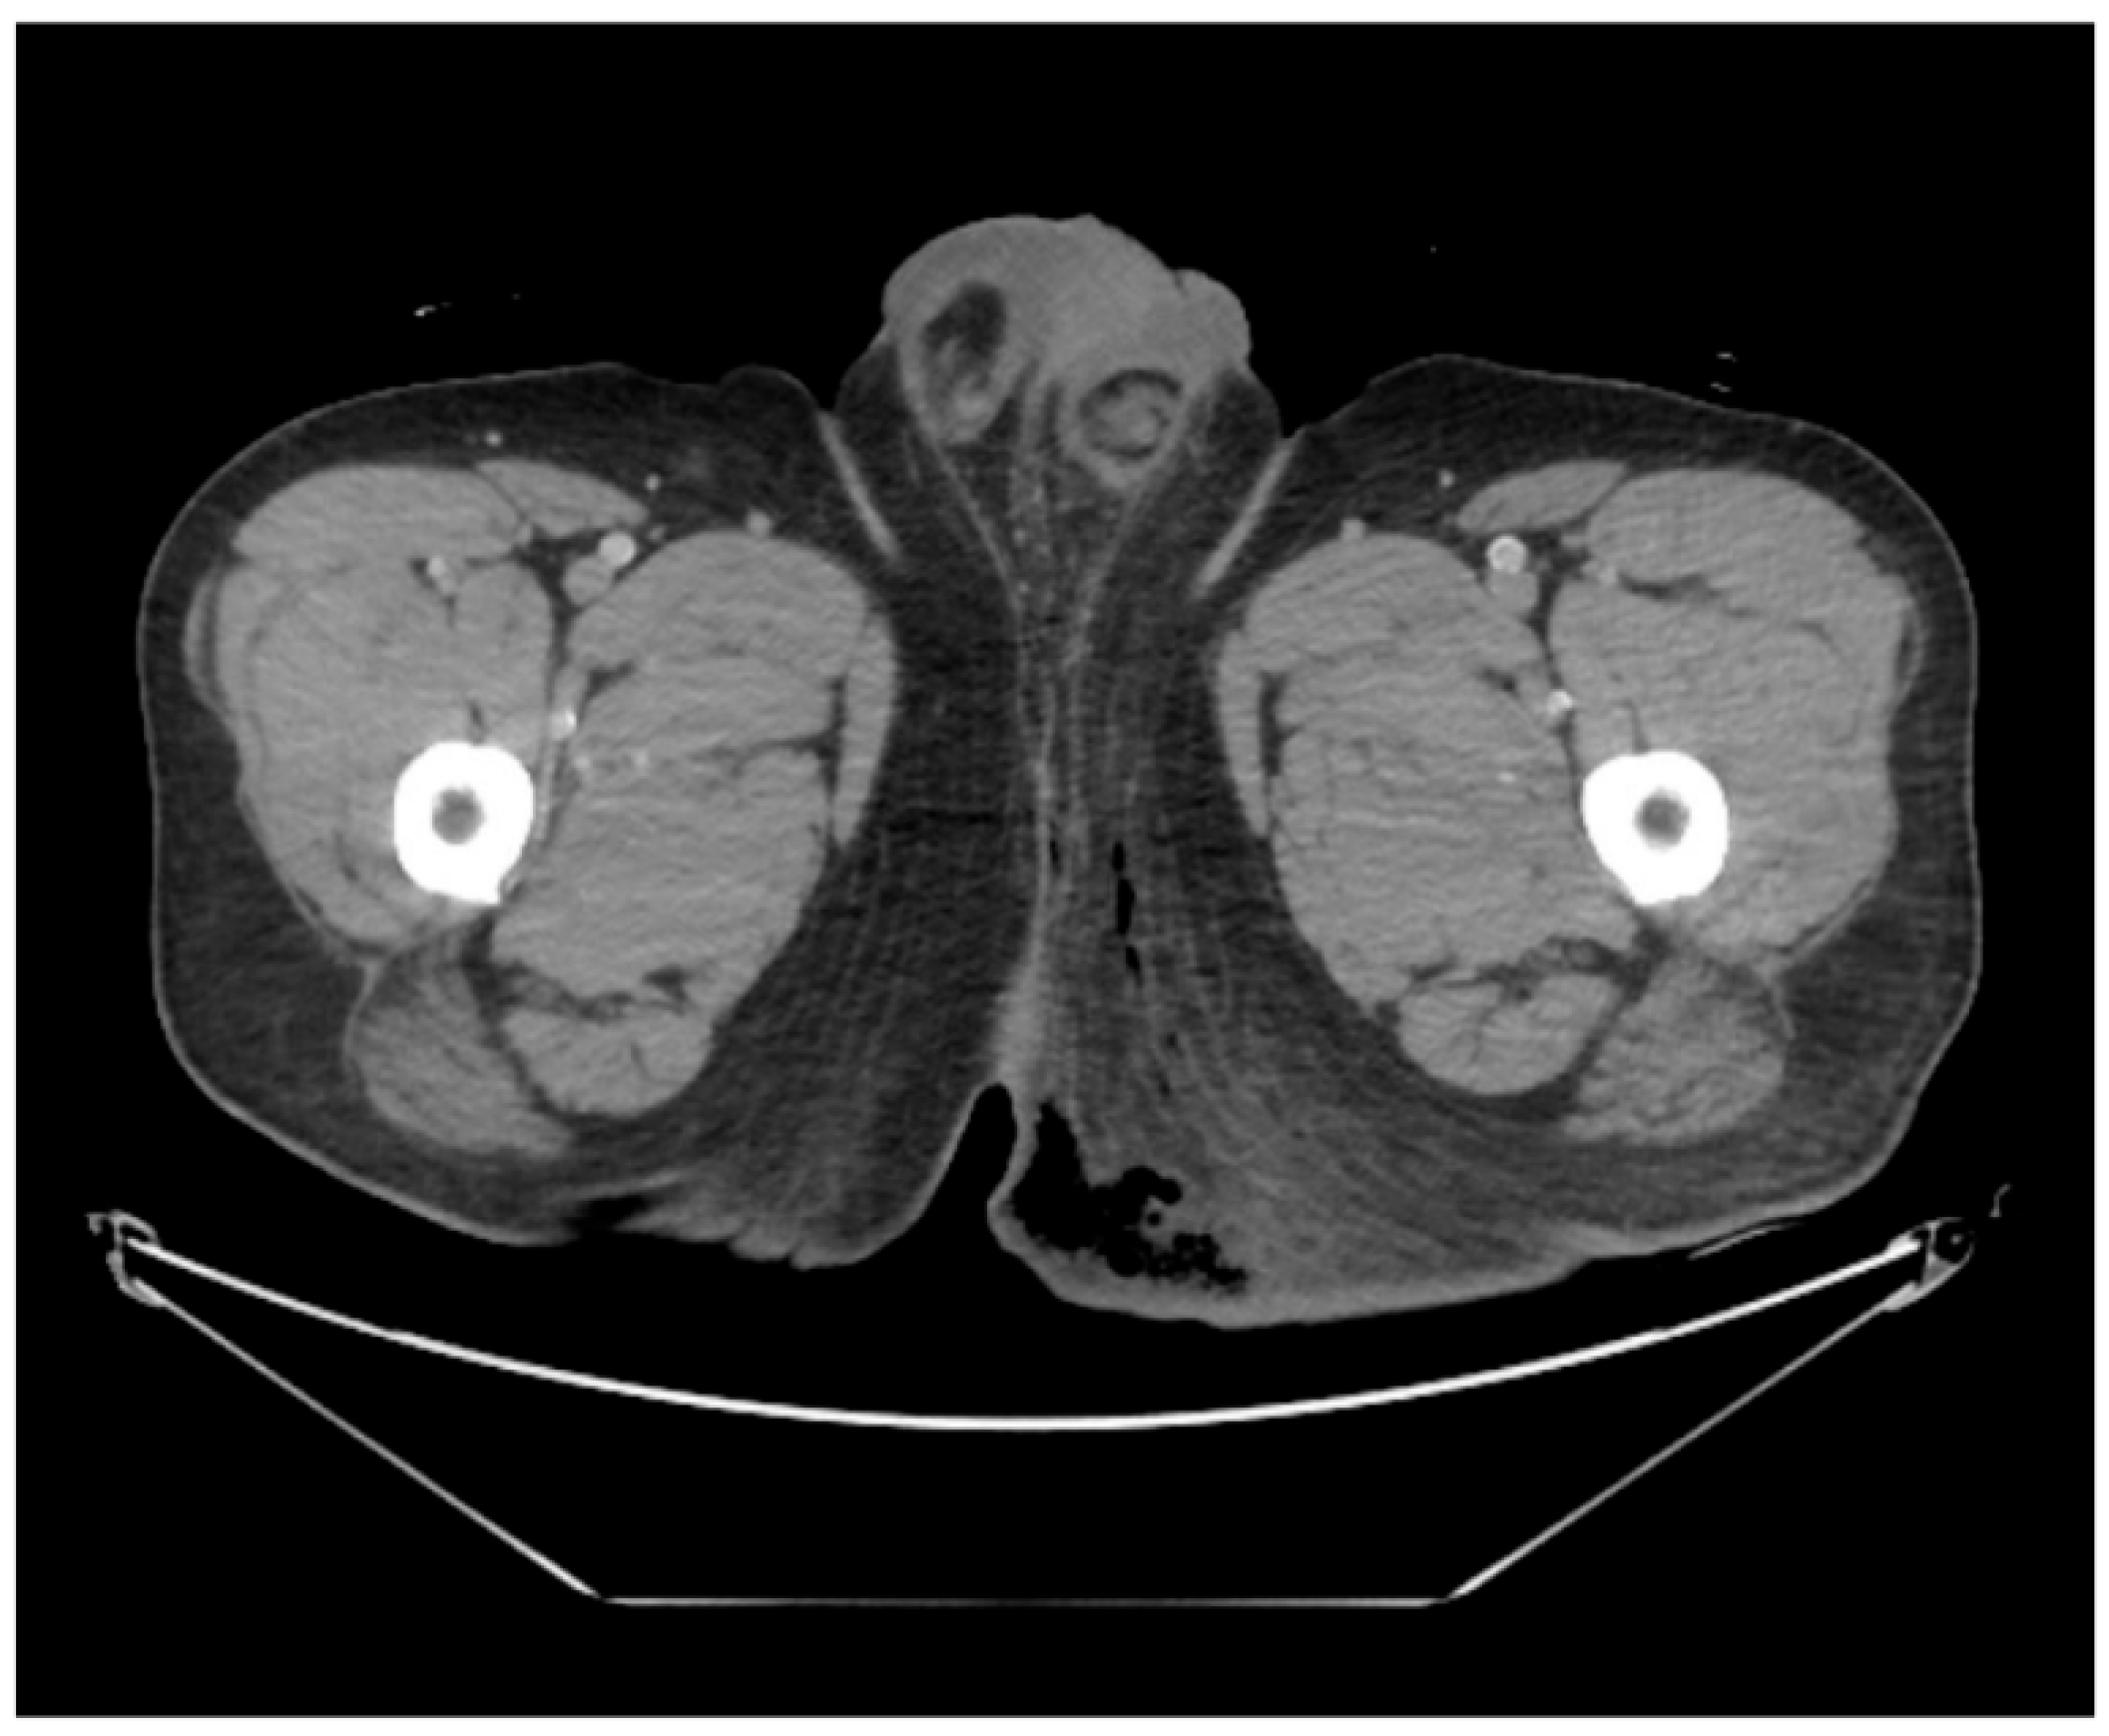

This case was conducted in accordance with the principles of the Declaration of Helsinki and was approved by the Institutional Review Board of Inje University Haeundae Paik Hospital (IRB No. 2023-12-028-001). Written informed consent for publication of clinical details and images was obtained from the patient. A 43-year-old male patient presented to the emergency department complaining of severe perineal pain and pus discharge from multiple sites in the perineum. The patient had undergone surgery for fistula at another clinic a week ago. He reported a medical history of diabetes, hypertension, and heavy alcohol consumption. Physical examination revealed an edematous scrotum with a foul-smelling exudate. Pelvic computed tomography (CT) revealed air collection in the buttock area, indicating Fournier’s gangrene (Figure 1). Baseline laboratory tests demonstrated marked leukocytosis (white blood cell count 22.74 × 109/L) with neutrophilia, elevated C-reactive protein (30.34 mg/L), and an increased serum lactate level (2.5 mmol/L), consistent with sepsis. Glycated hemoglobin was 7.2% and fasting glucose was 208 mg/dL, reflecting suboptimal glycemic control in a patient with known diabetes. Due to the aggressive nature of the condition and the development of sepsis, broad-spectrum antibiotics were promptly initiated. Subsequently, the patient underwent radical debridement in both the General Surgery and Urology departments.

Figure 1. Pelvic computed tomography scan in emergency room. The image reveals subcutaneous emphysema with fat infiltration in the left buttock and scrotum, suggesting Fournier’s gangrene.